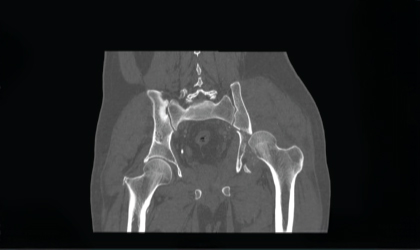

This 62 year old man had a fracture dislocation of his hip following a road traffic accident. He was referred to us two weeks later with a dislocated and fractured hip He underwent fixation of the fracure. The head was damaged and not viable after been dislocated for long. Hence he had a hip replacement as well These is a very complex surgery but he is back on his feet

On arrival, imaging revealed a severely dislocated hip with associated fracture. Due to the delay in treatment, the femoral head was non-viable and showed signs of damage.

We performed fixation of the fracture and, due to the compromised head of the femur, proceeded with a hip replacement during the same surgery. This complex procedure required precise alignment and implant positioning.